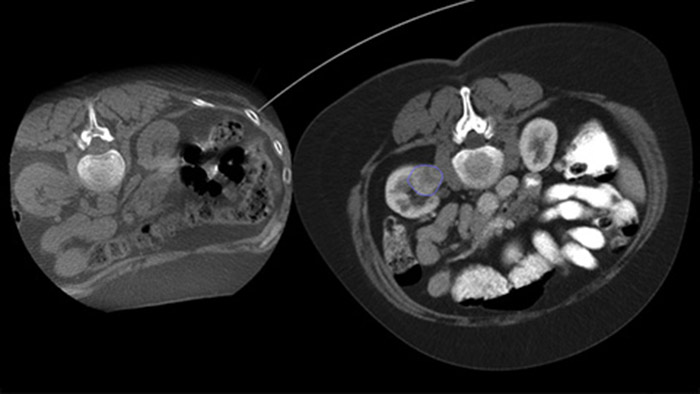

Чрескожная абляция (радиочастотная, микроволновая и криоабляция) — это зарекомендовавший себя малоинвазивный метод лечения опухолей почек, печени, легких и костей. Крайне важно определить границы опухоли, выбрать оптимальное количество игл и соответствующую траекторию для полного лечения опухоли без повреждения окружающих тканей. Прицельное продвижение к поражению при низкой дозе без изменения положения иглы увеличивает шансы на успех и снижает риск осложнений при биопсии или абляции. Проверить результат проведенной абляции можно с помощью 3D-визуализации, пока пациент находится на столе.

SmartCT Soft Tissue представляет собой метод получения КТ-подобных изображений, при котором процесс сопровождается пошаговыми инструкциями и расширенными инструментами 3D-визуализации и измерения; все элементы доступны на модуле сенсорного экрана прямо у стола.

Благодаря КТ-подобной визуализации возможно получение КТ-подобных изображений после абляции с целью определения степени охвата опухоли и подтверждения эффективности лечения.